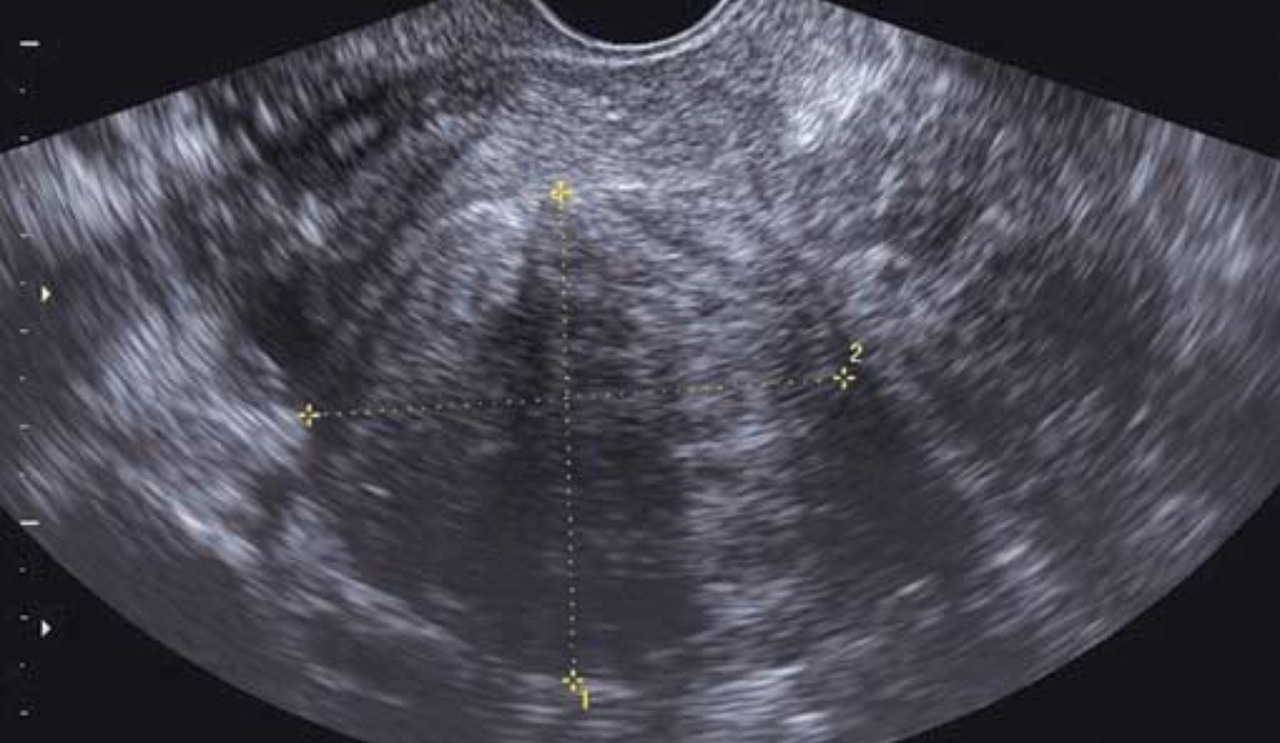

Échographie pelvienne (2D ou 3D)

Elle est toujours indiquée en cas d’hémorragie génitale d’origine haute, réalisée par voie sus-pubienne dans un premier temps, puis par voie endovaginale, vessie vide, dans un deuxième temps.Elle mesure la taille de l’utérus, qui est augmentée en cas d’adénomyose ou de fibrome.

Elle est utile à l’étude du myomètre, diagnostiquant fibromes (et leur cartographie) et adénomyose (fig. 2).

Elle permet le diagnostic des pathologies intra­cavitaires (telles que polypes endo-utérins et fibromes utérins), la mesure de l’épaisseur endométriale et apprécie la régularité de l’endomètre (cancer de l’endomètre).

Elle visualise les annexes et s’assure de la normalité de celles-ci.

Enfin, elle vérifie la présence ou non d’un épanchement dans le cul-de-sac de Douglas.

Le Doppler couleur couplé à l’échographie permet d’étudier la vascularisation de lésions organiques (pédicule de polype, fibrome).

Une échographie pelvienne est réalisée pour confirmer le diagnostic clinique et pour apprécier le volume utérin qui peut avoir des contours déformés par les léiomyomes. Les fibromes ont un aspect échographique caractéristique, arrondi, légèrement hypo­échogène par rapport au myomètre, avec vascularisation périphérique (fig. 5). L’échographie permet la cartographie des fibromes ainsi que le suivi de leur évolution.

L’adénomyose est une infiltration du myomètre, à partir de la cavité utérine, par des glandes endométriales. Typiquement, il s’agit d’une pathologie de la quarantaine chez une multipare. Les ménométrorragies sont souvent associées à des dysménorrhées sévères de fin de règles. Le toucher vaginal retrouve un utérus augmenté de volume de façon régulière, dur, lourd et sensible à la palpation. L’échographie permet d’évoquer le diagnostic en retrouvant un utérus augmenté de volume de façon assez diffuse avec souvent une disparité de taille entre le mur antérieur et le mur postérieur. Le myomètre apparaît hétérogène mais sans noyau myomateux nettement individualisable en son sein ; on peut aussi retrouver des images kystiques myométriales et des travées hyperéchogènes.